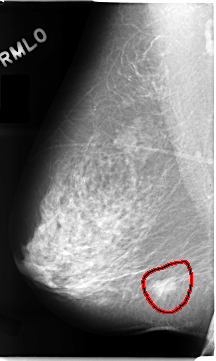

FILE: C_0102_1.RIGHT_CC.OVERLAY

TOTAL_ABNORMALITIES 1

ABNORMALITY 1

LESION_TYPE MASS SHAPE IRREGULAR MARGINS SPICULATED

ASSESSMENT 5

SUBTLETY 5

PATHOLOGY MALIGNANT

TOTAL_OUTLINES 1

BOUNDARY